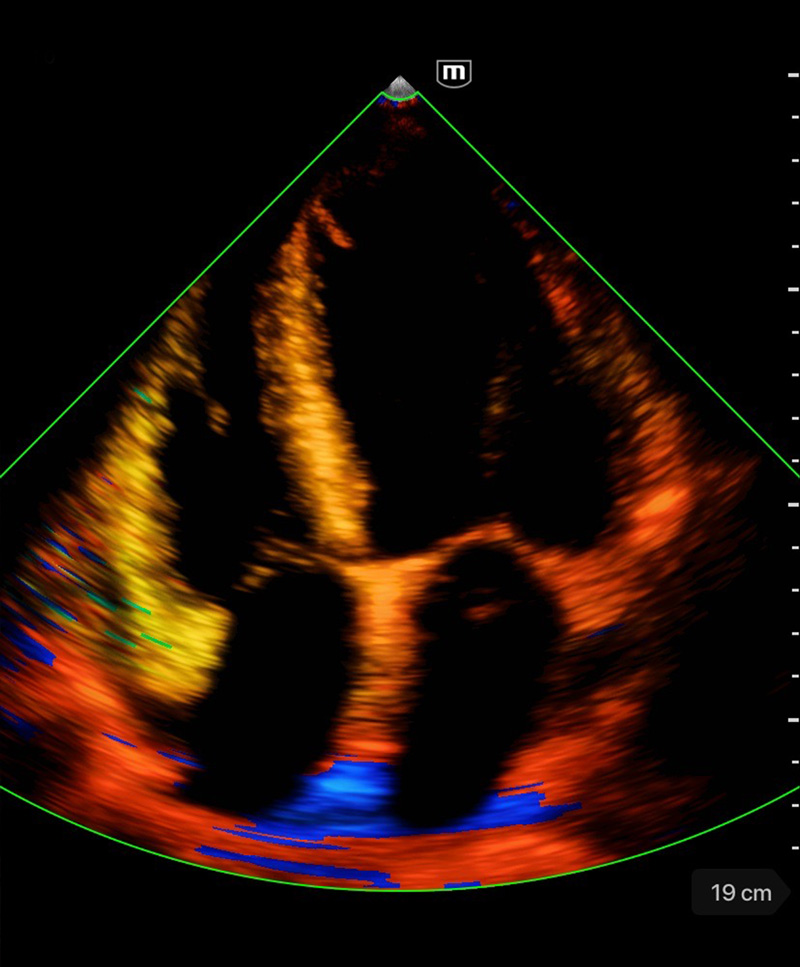

Immagini cliniche

Rigurgito mitrale e tricuspidale

Immagini cliniche

Rigurgito mitrale e tricuspidale